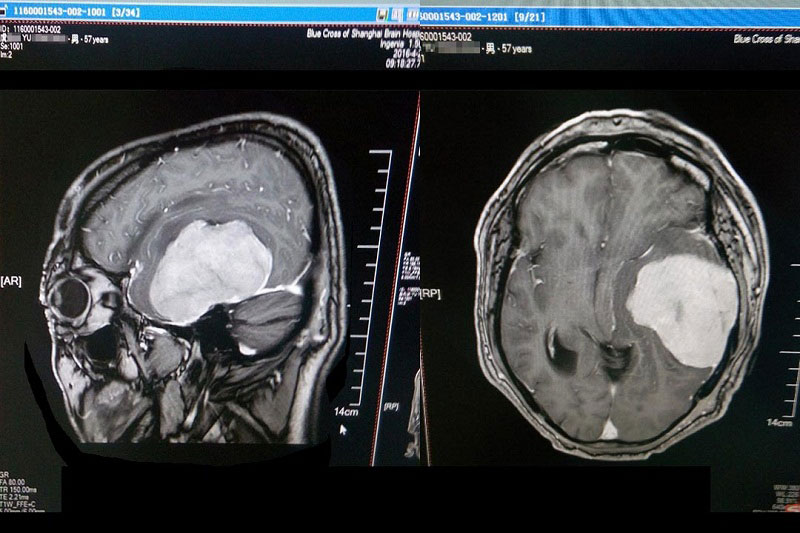

虞文军这才意识到问题的严重性,至当地医院就诊,行头颅CT检查示:左侧颞区底部大脑凸面可见类圆形略高密度占位病变,周围见低密度水肿影,CT值为44HU,大小约为8*6cm,周边脑组织及脑室受压,中线结构右移,额顶部软组织肿胀,考虑为左侧底部脑膜瘤。为求进一步治疗,经过四处打听,虞文军在爱人的陪同下于2016年4月22日前来上海蓝十字脑科医院就诊。

术前检查肿瘤清晰可见

患者入院后行头颅MR+增强及MRA发现:肿瘤供血丰富,供血起源于小脑幕上动脉。经包括沈建康教授在内的专家会诊后,考虑到患者脑肿瘤巨大(8*6cm)、肿瘤周边血供丰富,手术指征明确,常规手术切除恐出血过多,增加手术风险,决定术前先为虞文军行“超选择性全脑血管造影术+脑膜瘤供血动脉栓塞术”,对肿瘤供血动脉进行栓塞,减少出血量,再全麻下行“左侧颞底部巨大脑膜瘤切除术”。 沈建康教授表示:“ 我10年都没见过这么大的脑肿瘤了”。 患者术后随即恢复清醒,自我感觉头脑较前更清醒,语音、语速恢复较好,不到半个月便已能正常行走,顺利出院。